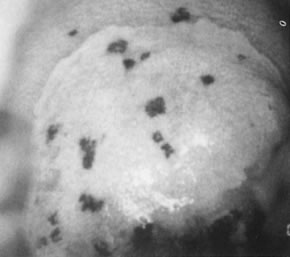

The surface may appear micropapillary (spiked), flat, or sometimes microconvoluted to a brainlike epithelial arrangement (Fig. 9). Many of the flat lesions have a pure, shiny-white color reminiscent of pearls, in contrast to the full, oyster-white color of high-grade cervical intraepithelial neoplasia (Figs. 10 and 11). Some HPV infections produce coarse capillary loops with a horizontal or vertical orientation, giving the appearance of a mosaic or punctation. The regular spacing of the vessels helps to differentiate these arrangements from invasive carcinomas.73,74 Histologically, the lesions contain koilocytotic and parakeratotic changes in the upper layers of the infected epithelium (Fig. 12).

Fig. 9. Colpophotograph of a spiked condyloma on the ectocervix. Myriad tiny excrescences cause the surface of the lesion to be irregular.